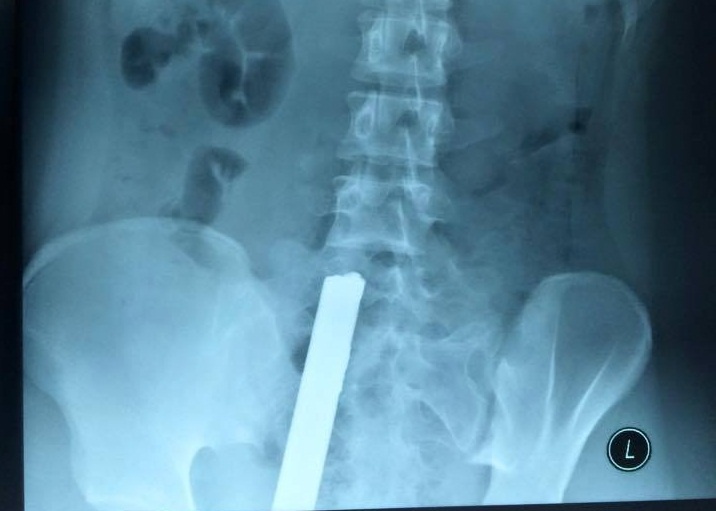

Bé trai bị thanh sắt đâm thủng tim khi rơi từ tầng 2

Bé Nam (5 tuổi) rơi từ ban công tầng 2 xuống đất và bị thanh sắt hàng rào đâm xuyên ngực, thủng tim, phổi. Gia đình phải nâng cơ thể bé khỏi hàng rào mới có thể đưa đi cấp cứu.